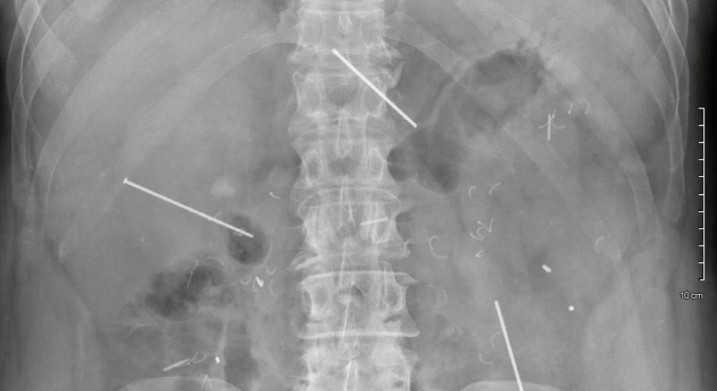

Оскільки біль зберігався, пацієнт повторно звернувся до медиків. Тоді йому призначили рентген черевної порожнини, який виявив у животі три сторонні тіла. Наступне КТ-обстеження показало, що три неушкоджені цвяхи були в районі печінки, підшлункової залози, дванадцятипалої кишки та тонкого кишечника.

Під час порожнинної операції хірурги виявили, що один із цвяхів пройшов через ліву частку печінки та середину підшлункової залози, а другий через праву частину печінки і зупинився недалеко від дванадцятипалої кишки. Третій, пройшовши через брижу тонкої кишки у лівій частині живота, застряг між петлями тонкого кишечника. Проте цвяхи витягли без витоку жовчі, панкреатичної рідини, пошкоджень кишківника чи інших негативних наслідків.